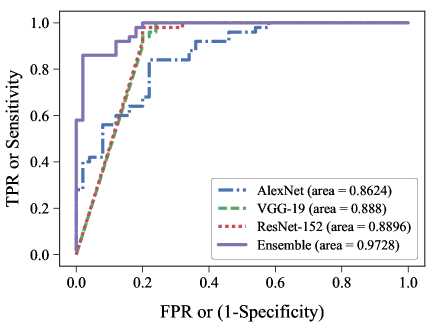

The ROC curves of one instance AlexNet, VGG-19, ResNet-152 and one ensemble model, that is linear average of 6 different types of DCNs, are shown in Fig. 6. The curves are obtained using 50 cardiomegaly and 50 normal images. The AUC obtained for each model are , , and , respectively. We can understand from the AUC values that, the separation between the pathology class and the normal class increases when an ensemble of multiple DCNs are performed. For the ensemble model to be used as a screening tool with high sensitivity, the operating point on the curve is set to achieve sensitivity. The specificity obtained at this point is . The second operating point is set for high specificity of and the sensitivity at this point is .